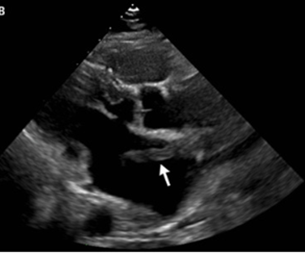

心エコーでは血栓が卵円孔を通って、左心房にまさに通過しているところが示された。